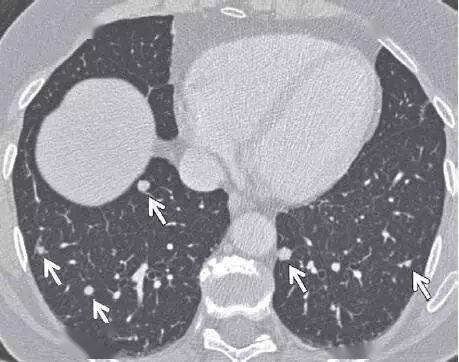

医影基础丨14 种经典肺结节影像,必须要看

肺磨玻璃结节

磨玻璃结节